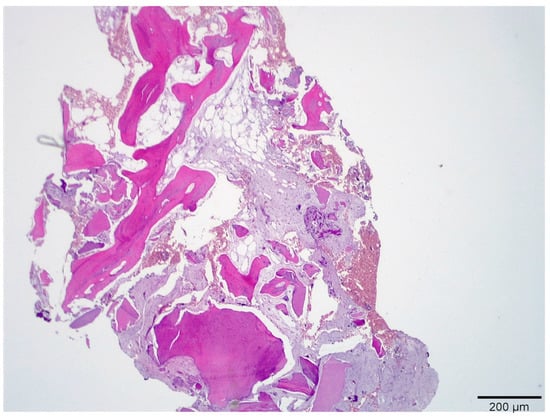

3.1. Histological Analysis Showed Signs of New Bone Formation at 60 Days

3.2. Histologic Data Obtained after Samples Analysis at 24 Months of Evaluation

| New bone | 16.3 ± 1.98 | 41.1 ± 0.76 | 54.5 ± 0.24 | 59.4 ± 1.23 * |

| Residual Graft | 37.1 ± 0.34 | 30.0 ± 0.45 | 21.3 ± 0.88 | 15.6 ± 086 |

| Connective tissue | 46.6 ± 0.11 | 29.9 ± 0.56 | 24.2 ± 0.32 | 25.0 ± 0.44 |